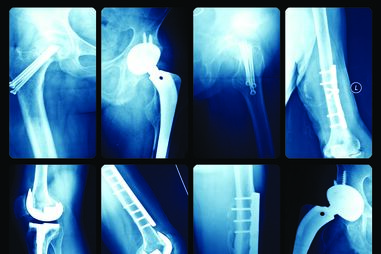

Ao longo da vida, quer pelo tipo de profissão, passado desportivo ou hereditariedade, o nosso corpo vai envelhecendo e desgastando as cartilagens que revestem as nossas articulações